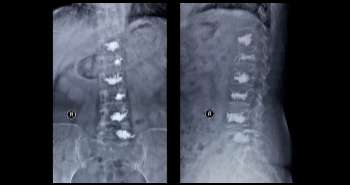

Pain is severe burden for rheumatoid arthritis (RA) patients. But, the effect on the Health Assessment Questionnaire Disability Index (HAQ-DI) and 28-joint Disease Activity Score (DAS28) was to be evaluated thus this study aimed to examine them in a case series.

A total of 384 patients who were treated for more than 5 years were studied. The parameters investigated comprised of the HAQ-DI score, average value of the DAS28 with C-reactive protein (DAS28-CRP), Sharp/van der Heijde Score (SvdHS), age, and the pain score calculated by a PS-VAS. Relationships among these factors and relationships between the HAQ-DI score and the other factors, and between the change in HAQ-DI scores and changes in other factors were evaluated statistically using the multivariate linear regression analysis. The effect of PS-VAS on HAQ-DI was compared with that of DAS28-CRP on the overlapping data of each parameter.

HAQ-DI revealed significant positive correlations with all the parameters. However, PS-VAS demonstrated a stronger effect than DAS28-CRP, also confirmed without overlapping data. After curtailing the impact of DAS28-CRP, age and SvdHS, there was a significant correlation between HAQ-DI and PS-VAS in all the analyses. The change in HAQ-DI demonstrated a significant association with the change in PS-VAS.

The results portrayed that PS-VAS profoundly influences HAQ-DI. The effect of DAS28-CRP overlapped with the impact of PS-VAS in a significant way. The pain control for RA patients is the most critical factor contributing to activities of daily living, as well as disease activity control.